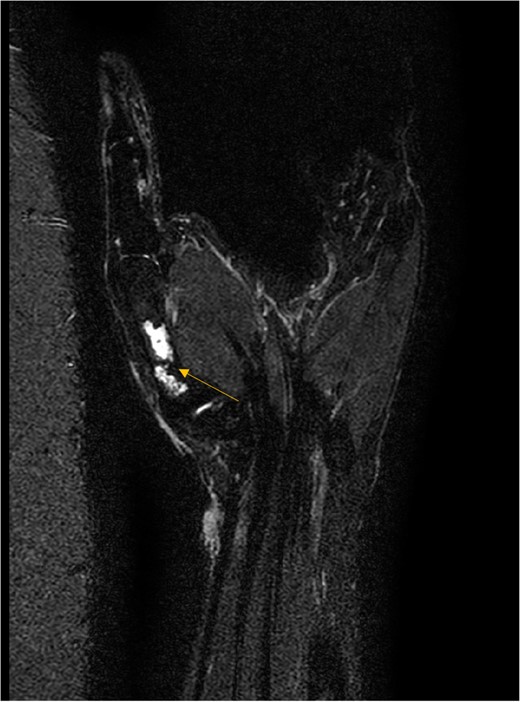

X-ray showed a well-defined non-aggressive lytic bony lesion of the first metacarpal bone (Fig. 1). Magnetic resonance imaging (MRI) showed a grossly stable skin and subcutaneous multilobulated soft tissue mass located at the palmar aspect of the wrist joint measuring 6 × 2 × 3.3 cm3 in its maximum anteroposterior, transverse and craniocaudal dimensions, respectively (Figs 2 and 3). The lesion showed low and high signals in T1 - and T2-weighted images with homogenous contrast enhancement. The lesion was inseparable from the flexor carpi radialis and palmaris longus tendons without definite invasion or encasement. The lesion was not in continuity, however, with the serpiginous lytic bony lesion noted at the first metacarpal bone exhibiting low T1 and high T2 signals with peripheral enhancement and no cortical destruction or associated soft tissue component (Fig. 4).

MRI of the left distal forearm showing cutaneous and subcutaneous lobulated mass at the volar aspect of high T2 and low T1 signals with diffuse enhancement. (A) Sagittal T2-weighted fat saturated image. (B) Sagittal T1-weighted image.